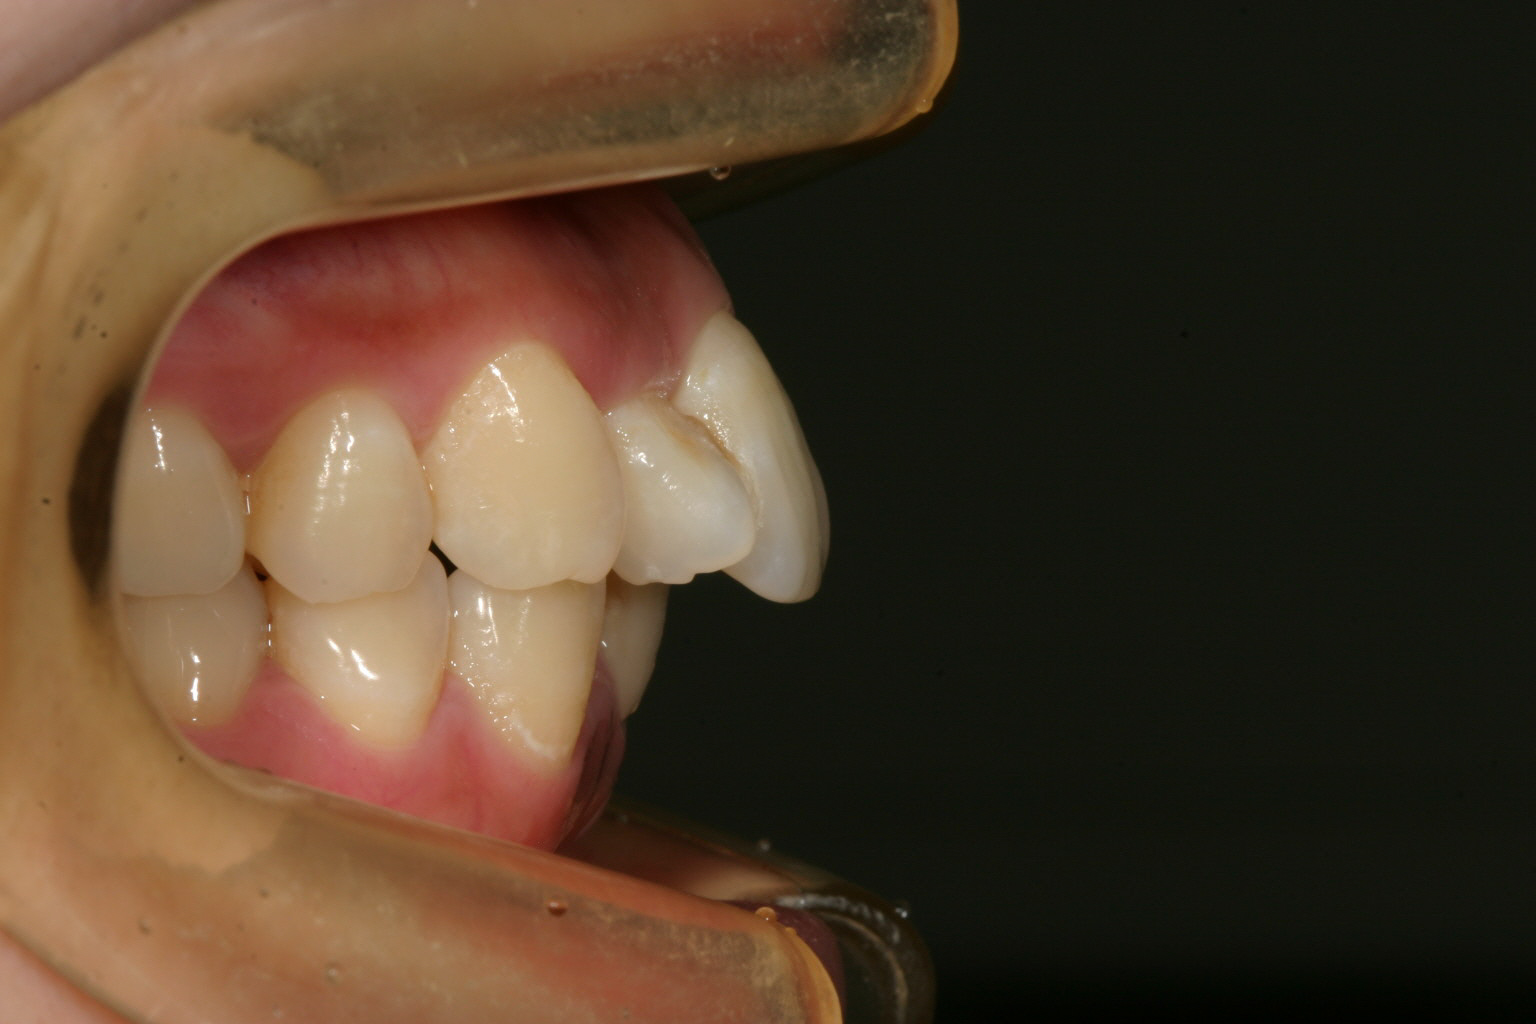

アーチフォームは綺麗ですが右上の2番目がちょっと横向いてます。

少し出っ歯観が気になりますね~